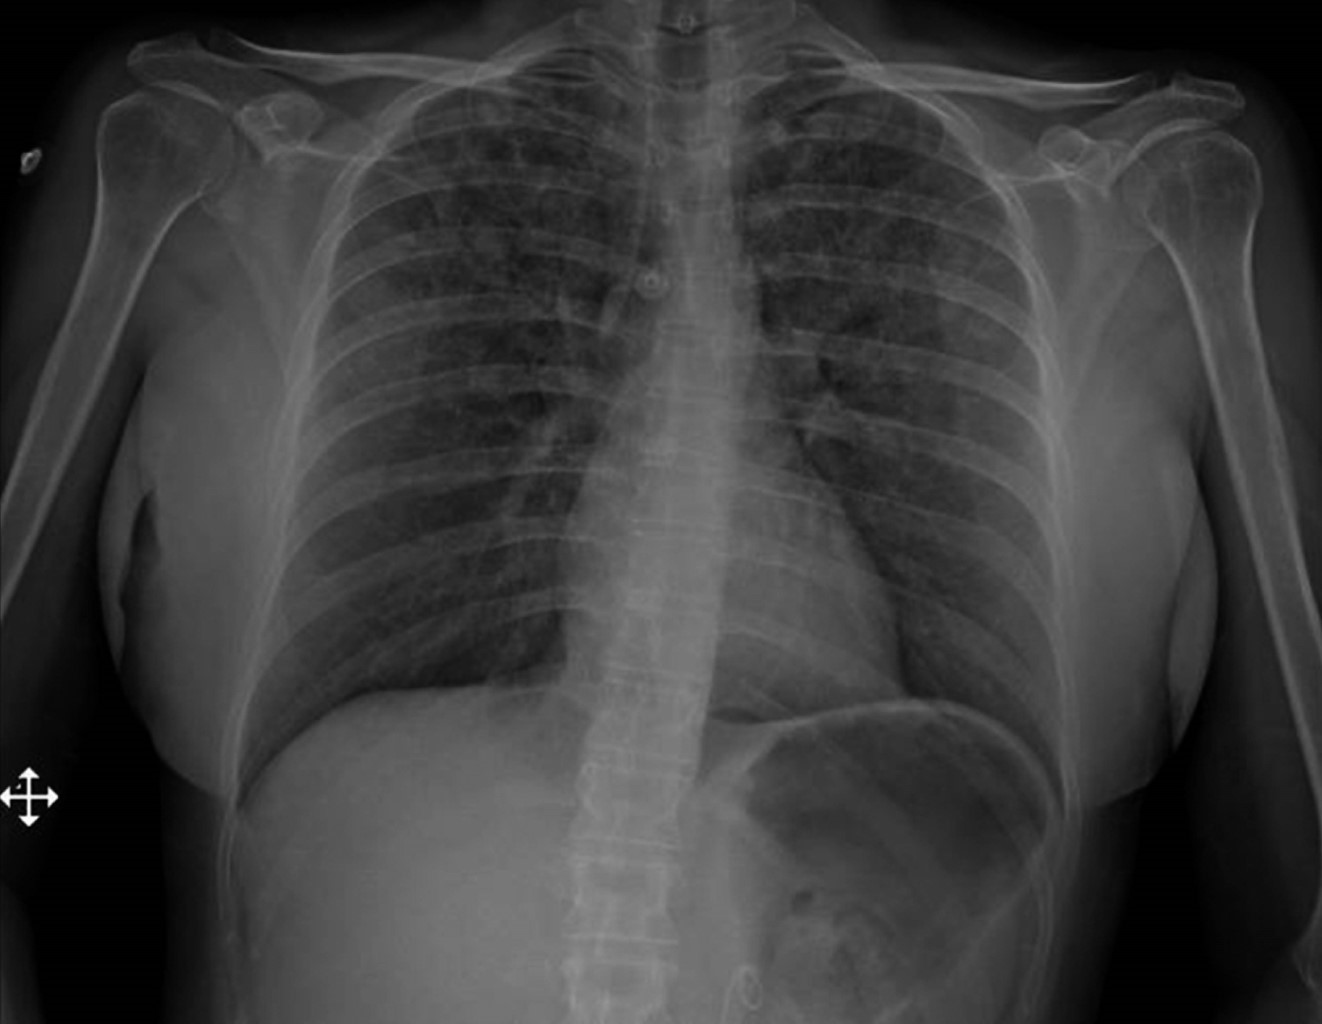

Una mujer de 47 años de edad sin antecedentes médicos se sometió a cirugía endourológica programada. Al ingreso a quirófano, se encontraba en buen estado general, con signos vitales y exploración física normales. Se aplicó anestesia general balanceada, realizando inducción con fentanilo, propofol, rocuronio y durante laringoscopia sin evidencia de anomalías. Orotubación se realizó sin complicaciones al primer intento con hoja número 3 y tubo número 7, cursa hemodinámicamente estable, sin necesidad de apoyo vasopresor con solución Hartmann intravenosa a 20 mL/h sin necesidad de mayor reanimación hídrica, ventilación de protección tidal, mantenimiento con sevorane y fentanilo en infusión calculado a 2 μg/kg/h, ventilación pulmonar simétrica y valores adecuados en capnografía postintubación. Durante el procedimiento quirúrgico sin aumento de presiones o desacoplamiento a ventilación mecánica. La paciente presentó agitación espontánea al recobrar conciencia realizando esfuerzos inspiratorios importantes con laringoespasmo breve de cuarenta segundos. La extubación presentó disminución de agitación y sin deterioro del patrón respiratorio; durante la hora de vigilancia postoperatoria, sin deterioro cardiorrespiratorio. Sin embargo, dos horas posteriores a extubación, la paciente mostró signos de dificultad respiratoria: taquipnea, uso de musculatura accesoria, desaturación al 70% al aire ambiente, estertores crepitantes bilaterales; radiografía de tórax portátil reveló evidencia de edema agudo pulmonar (Figura 1). La administración de oxígeno suplementario logró aumentar saturación hasta 92%. Ante sospecha de edema pulmonar de presión negativa, se realizaron ecocardiograma transtorácico y angiotomografía de tórax, sin evidencia de falla cardiaca ni tromboembolia pulmonar. Se optó por utilizar puntas nasales de alto flujo, diurético de asa, nebulizaciones con β-agonistas y terapia pulmonar. La paciente evoluciona de manera satisfactoria (Figura 2), dándose de alta al tercer día postoperatorio.

Figura 2